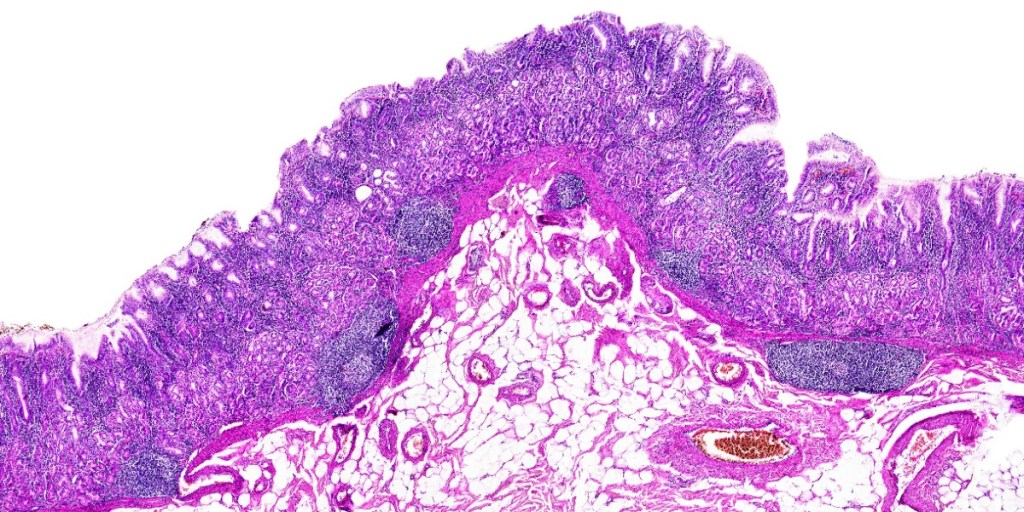

Colour is important. Clever choice of colour can provide definition, interest, depth and mood. Colour can make things pop and not just in art. Histological interpretation of tissue samples will be important to all of us one day. To surgeons it is important virtually every day. We need a correct diagnosis, assessment of the success of our work and a heads up about how a disease, particularly tumours, can be expected to behave. The classic tissue stain in pathology is H&E. Haematoxylin and Eosin is actually two dyes, developed independently in 1865 and 1875, respectively by Bohmer and Fischer. In 1876, Wissowzky had the bright idea to combine them so that dull tissue sections would be easier to interpret. Haematoxylin is a cationic aluminium salt and acts as a basic dye. It stains nucleic acids in the cell nucleus a blue/purple hue. Eosin is anionic and an acidic dye. It is negatively charged and stains protein amino groups in cell cytoplasm bright pink. #thebasisofwhatido #letsmakelemonade